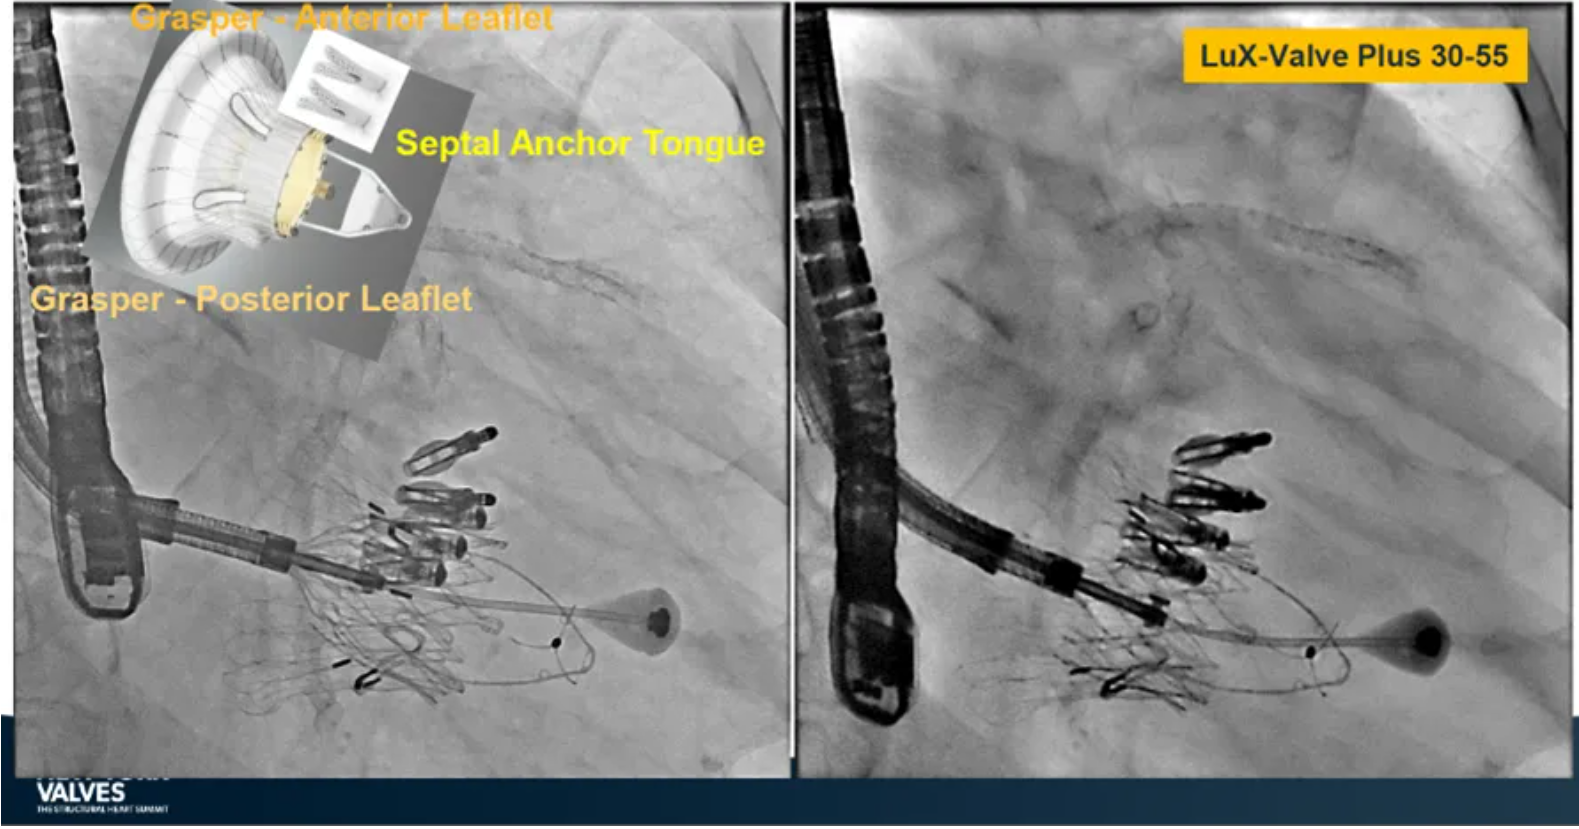

Granada教授表示,LuX-Valve Plus是一款不依賴于徑向支撐力固定的多功能TTVR器械,它的創(chuàng)新設(shè)計(室間隔錨定和瓣葉夾持件)提供了多樣的固定和穩(wěn)定技術(shù)。多中心臨床試驗研究TRAVEL II 展現(xiàn)了LuX-Valve Plus的安全性和有效性,能實現(xiàn)較短的器械操作時間,較低的復(fù)合事件發(fā)生率,并在6個月期時顯著降低三尖瓣反流等級,以及帶來心功能和生活質(zhì)量等指標(biāo)上的明顯改善。

來自法國波爾多大學(xué)醫(yī)院(CHU de Bordeaux, Bordeaux, France)的Thomas Modine教授在2024紐約瓣膜會上介紹到針對目前三尖瓣反流臨床上的痛點,包括大瓣環(huán)、起搏器或者心臟除顫器ICD導(dǎo)線的影響、依賴術(shù)中影像,以及術(shù)后起搏器的植入等,LuX-Valve Plus都能夠提供良好的解決方案。他在最后總結(jié)道,LuX-Valve Plus創(chuàng)新的設(shè)計能夠有效降低術(shù)后的并發(fā)癥,例如起搏器植入率和血栓的形成。同時,TRAVEL II 研究的6個月期數(shù)據(jù)也體現(xiàn)了產(chǎn)品較短的器械操作時間,較低的復(fù)合事件發(fā)生率,顯著改善的心功能和生活質(zhì)量,以及能夠跟術(shù)前就已經(jīng)存在的起搏器導(dǎo)線兼容的優(yōu)勢。

來自中國上海復(fù)旦大學(xué)附屬中山醫(yī)院的魏來教授在2024年臺北瓣膜高峰論壇上分享了他使用LuX-Valve Plus治療三尖瓣反流的經(jīng)驗。魏來教授闡述道,隨著療法演變,目前全球市場有以LuX-Valve Plus及其他產(chǎn)品為代表的經(jīng)導(dǎo)管三尖瓣介入置換系統(tǒng),逐漸成為重度三尖瓣反流的一線治療方案。他介紹到,LuX-Valve Plus創(chuàng)新的室間隔錨定和經(jīng)頸靜脈入路的方式,能夠帶來安全穩(wěn)定的錨定效果及較短的輸送行程;其可調(diào)彎的輸送系統(tǒng)能保證同軸性,從而快速和安全地將人工瓣膜送達(dá)目標(biāo)手術(shù)區(qū)域,有效降低入路周邊解剖組織并發(fā)癥及術(shù)中出血風(fēng)險。